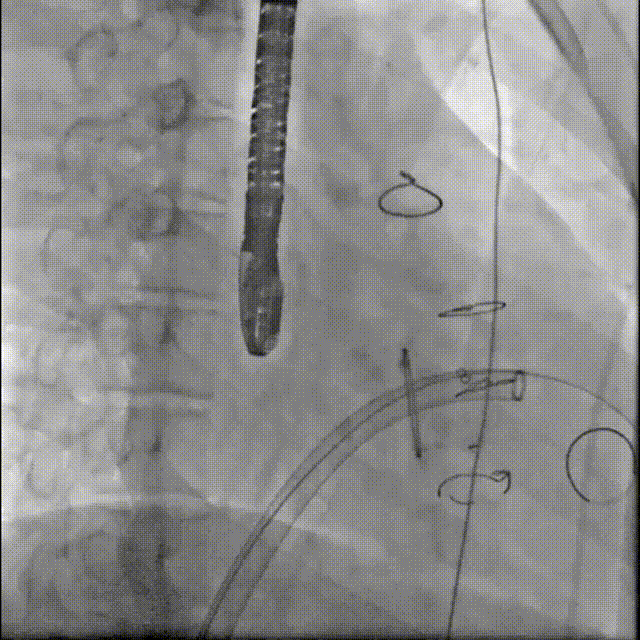

预弯鞘定位

置入26mm Prizvalve

撤出大鞘,Prizvalve瓣膜显影点定位

Prizvalve瓣膜左侧显影点与瓣环齐平后球囊扩张释放瓣膜

术后造影三尖瓣反流消失